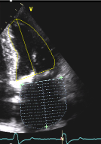

- Specific analysis services: Angiography (coronary and peripheral),Intravascular imaging (OCT- IVUS), QFR, iFR, MRI, Echocardiography (TTE, TEE), CT-scan (aortic & mitral valves, peripheric), Cardiac MRI, ECG and, aortography.

- Quantitative and qualitative assessments (Angiography, QCA, IVUS, OCT, QFR, ECHO, CT scan, MRI, ECG)

Echocardiography (TTE)